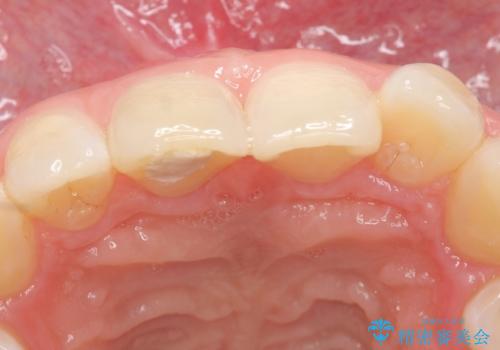

- 他院にて根管治療を行っていたが、痛みが引かないので診て欲しいといらっしゃった方の症例です。

マイクロスコープ下でラバーダムを使用しながら根管治療を行い、痛みが治まった後にオールセラミッククラウンによる補綴を行いました。

今回用いたオールセラミッククラウンはジルコニアフレームという白い素材の上にセラミックを盛っているため、審美性が非常に高いのが特徴です。

また、ジルコニアは人工ダイヤモンドの材料にも使われているほど高い強度を持っており、そのためオールセラミッククラウンは審美性だけでなく、奥歯やブリッジの補綴も可能とするクラウンです。